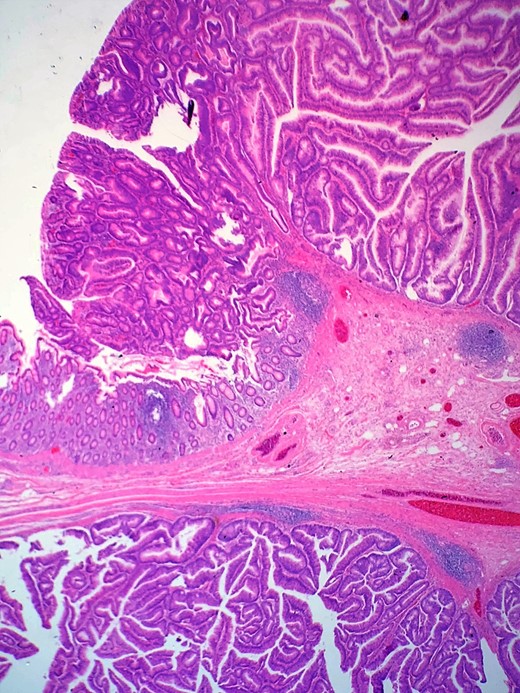

Definitive histological examination showed perforated appendix involved by moderately differentiated mucinous adenocarcinoma (Fig. 5), arising in the background of diffuse tubulovillous adenoma with extensive high-grade dysplasia and showed cellular mucin within the periappendiceal soft tissue (Figs 6 and 7). Proximal cecal mucosal margin and mesenteric margin uninvolved by carcinoma and four periappendicular lymph node was negative for metastatic carcinoma and pathological stage aided for pT4a, pN0. The post-operative course was uneventful. The tumor was staged as T4N0M0 (Modified Astler Coller B3). Patient was referred for oncology and for multidrug adjuvant chemotherapy of 5-fluorouracil, lecovorin and oxalipatin (FOLFOX) was given. Patient was asymptomatic during the 2 weeks, 3 months and 6 months follow up.

This demonstrates mucinous tumor with pushing invasion through the appendiceal wall.

Shows transition of normal cecal mucosa to high-grade tubulovillous adenoma at the appendiceal orifice.